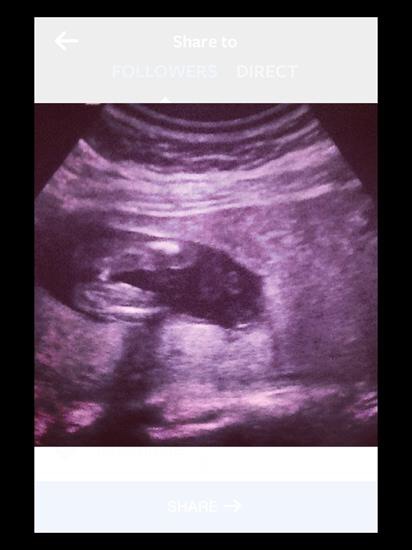

The second pic is a potty shot at 17 weeks!